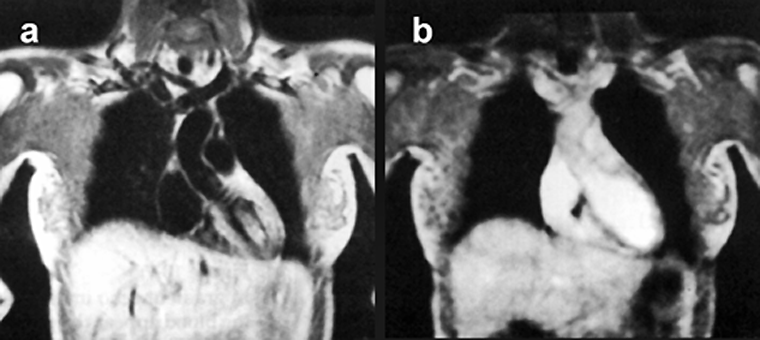

Figure 14-09 shows an example of high-signal blood in an examination of the pelvis. This behavior has been exploited for cardiac studies (Figure 14-10) and is fun­da­­men­tal to magnetic resonance angiography.

Figura 14-09:

In gradient-echo images, flowing blood appears bright. Note: These images are plain GRE ima­ges; they are not (yet) MR angiograms. Parameters: B₀ = 0.5 T; TR = 400 ms, TE = 28 ms, FA = 20°.